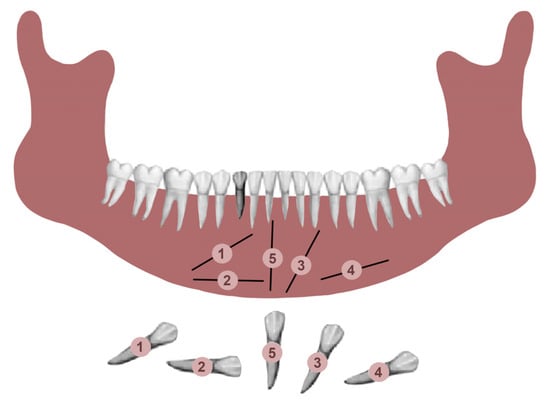

A total of 25 patients with mandibular canine impaction were found in Group A. Of these 25 patients, 14 were male and 11 were female. Canine impaction was bilateral in 12 patients and unilateral in 13 patients, with a total of 37 impacted permanent mandibular canine teeth. 21 impacted canines were found on the left side, and 16 canines on the right. 16 patients (64%) had retained deciduous canines at the time of diagnosis. In three cases, the impacted canines were transposed in the lateral incisor region. In one of the patients, there was a supernumerary tooth in the lateral incisor region, and the primary canine was still present in the dental arch (Figure 2). In one patient in whom the primary canine and primary lateral incisor were retained, impaction of both the lower permanent canine and lower permanent lateral incisor was noted. One patient was found to have complete impaction of all four canines. None of the patients had traumatic episodes, and none of them had systemic disorders. All the patients were asymptomatic.

Figure 2.

Mandibular impaction of left canine and presence of a supernumerary tooth.